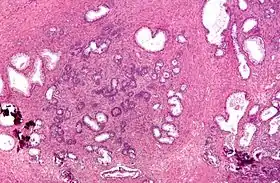

Both the glandular epithelial cells and the stromal cells (including muscular fibers) undergo hyperplasia in BPH.[2] Most sources agree that of the two tissues, stromal hyperplasia predominates, but the exact ratio of the two is unclear.[42]:694

Anatomically the median and lateral lobes are usually enlarged, due to their highly glandular composition. The anterior lobe has little in the way of glandular tissue and is seldom enlarged. (Carcinoma of the prostate typically occurs in the posterior lobe – hence the ability to discern an irregular outline per rectal examination). The earliest microscopic signs of BPH usually begin between the age of 30 and 50 years old in the PUG, which is posterior to the proximal urethra.[42]:694 In BPH, the majority of growth occurs in the transition zone (TZ) of the prostate.[42]:694 In addition to these two classic areas, the peripheral zone (PZ) is also involved to a lesser extent.[42]:695 Prostatic cancer typically occurs in the PZ. However, BPH nodules, usually from the TZ are often biopsied anyway to rule out cancer in the TZ.[42]:695 BPH can be a progressive growth that in rare instances leads to exceptional enlargement.[43] In some males, the prostate enlargement exceeds 200 to 500 grams.[43] This condition has been defined as giant prostatic hyperplasia (GPH).[43]